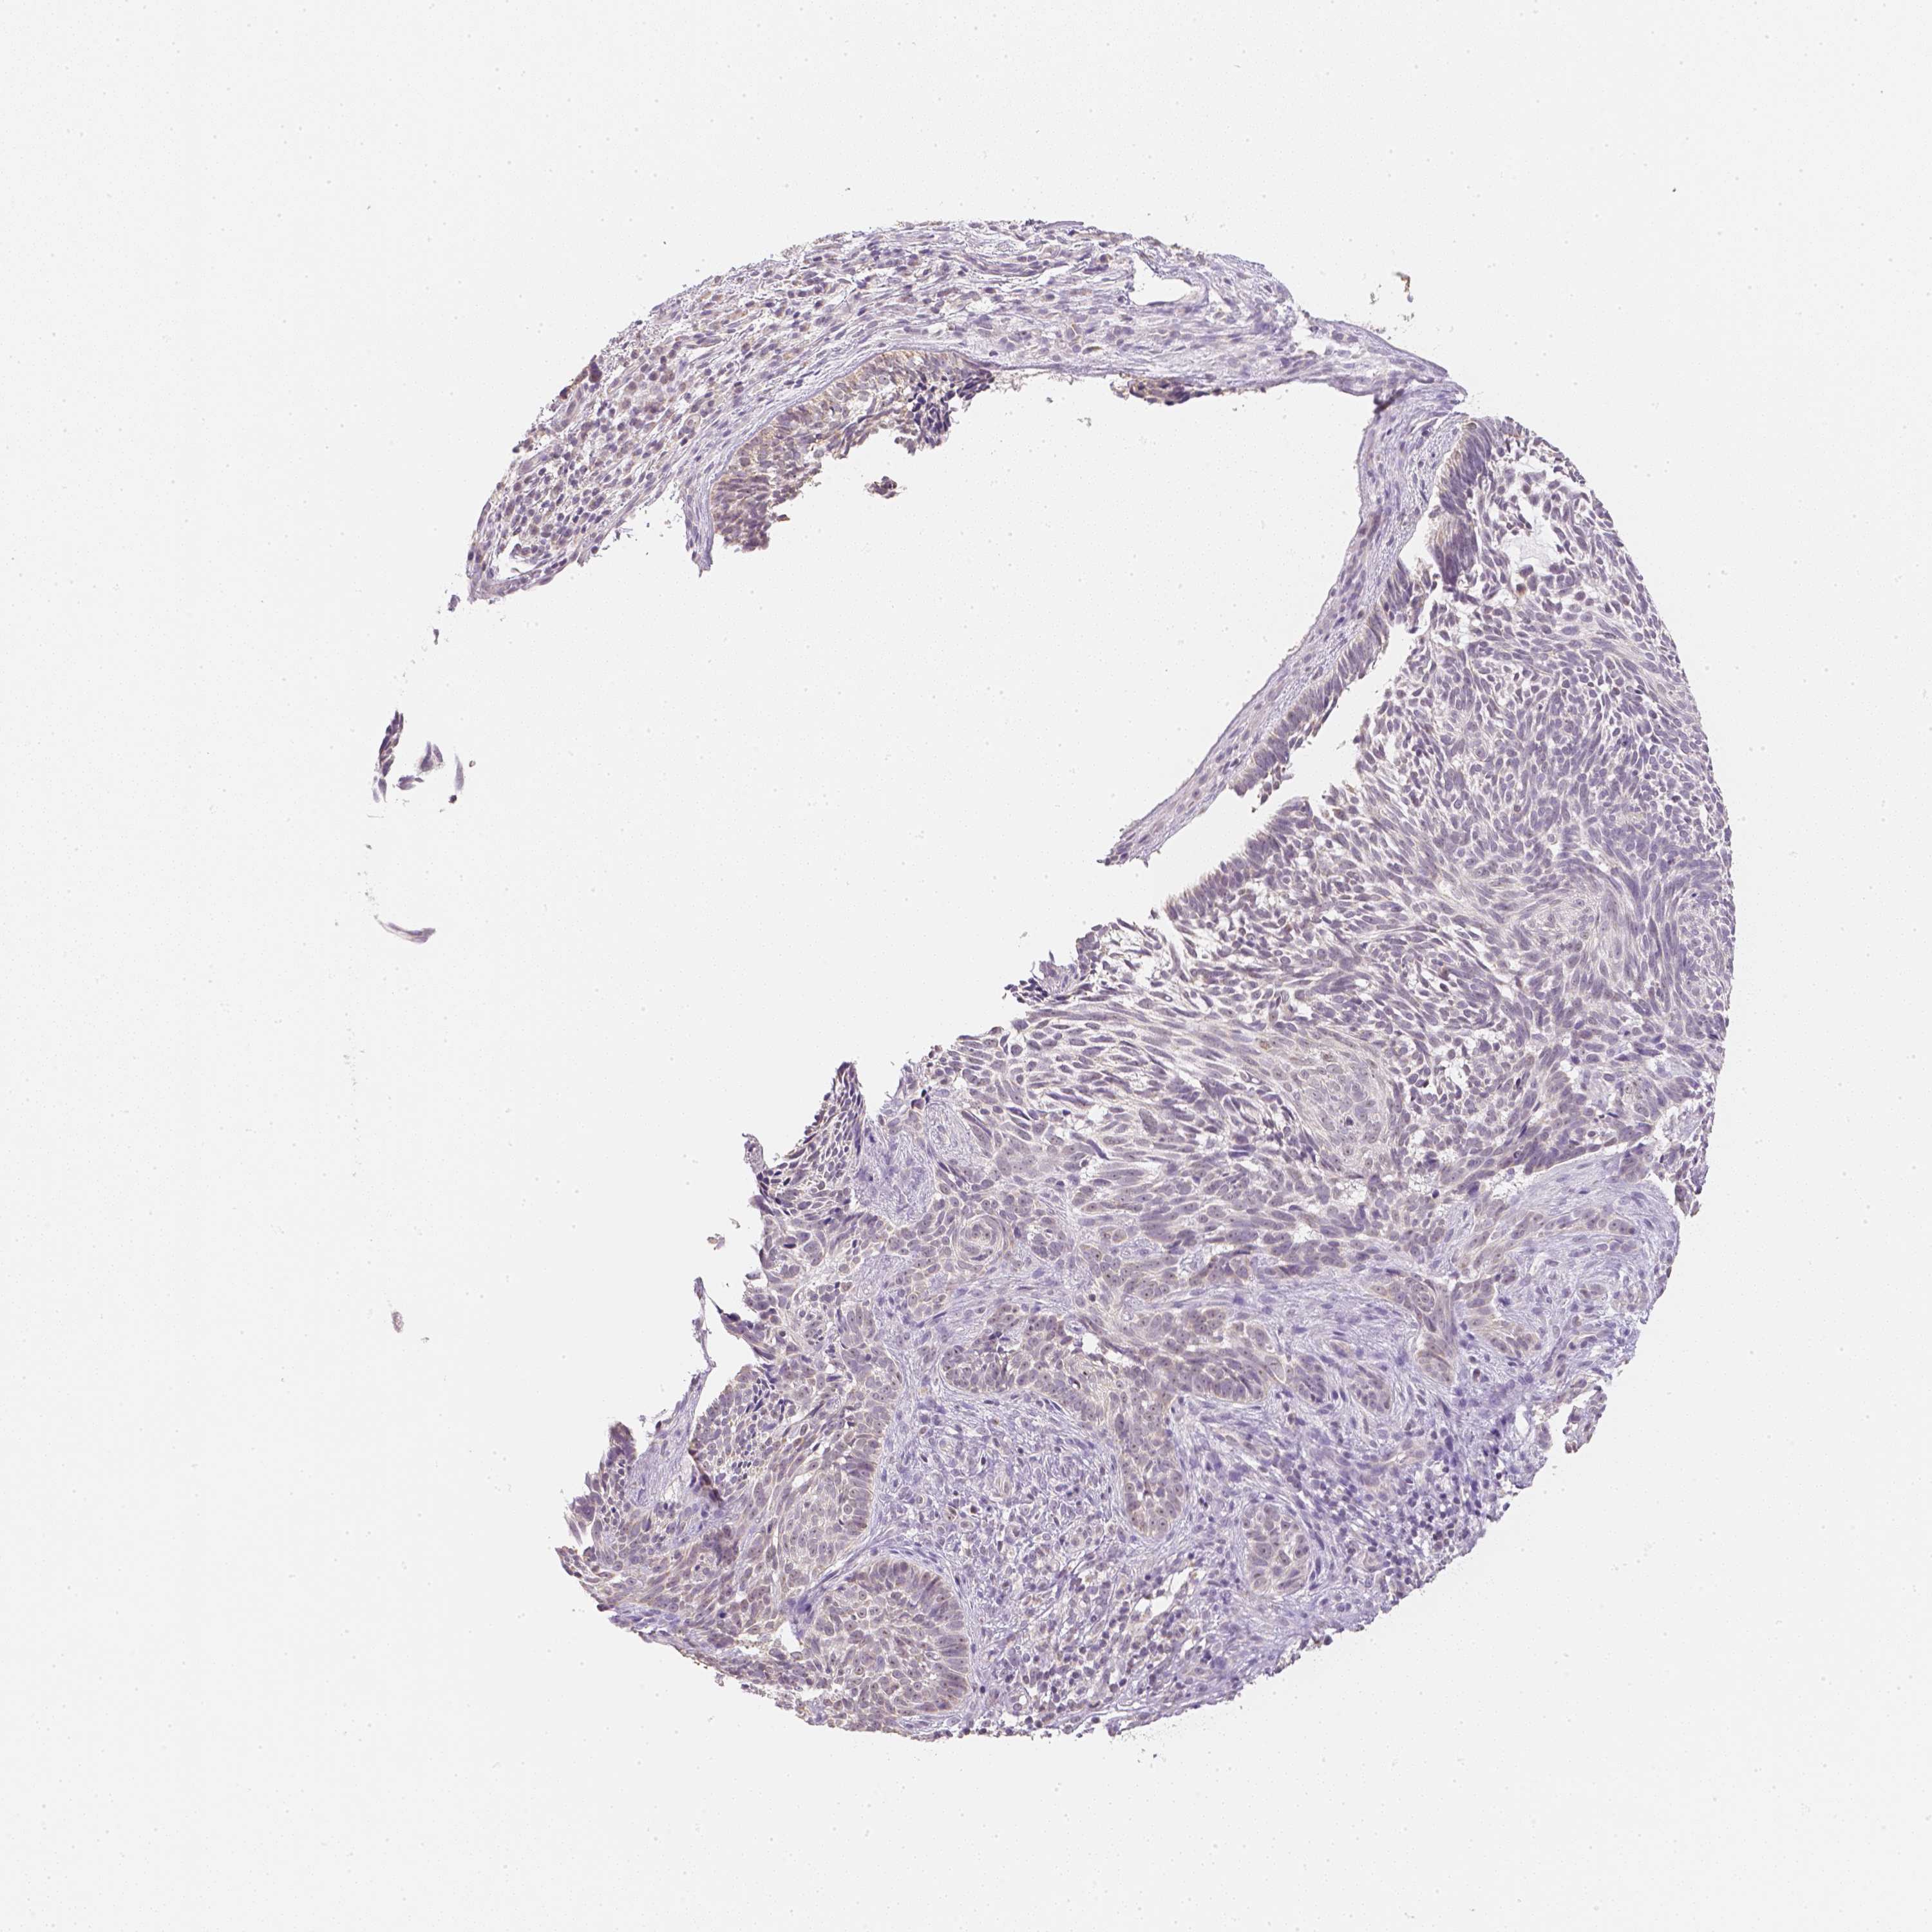

CANCER SKIN CANCER Show tissue menu

Basal cell and squamous cell cancer

SKIN CANCER - Protein expressioni

A mouse-over function shows sample information and annotation data. Click on an image to view it in a full screen mode. Samples can be filtered based on level of antibody staining by selecting one or several of the following categories: high, medium, low and not detected. The assay and annotation is described here.

Each image is clickable and will lead to virtual microscopy that enables deeper exploration of all samples and also displays staining intensity scores, fraction scores and subcellular localization as well as patient and tissue information for each sample.

Antibody HPA028207

Basal cell carcinoma